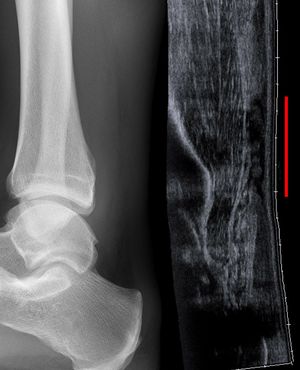

![]() صورة خلفية للقدم والساق، توضح وتر أخيل. | |

صورة خلافية للكاحل البشري، ويشمل وتر أخيل. | |

التصوير الشعاعي يمكن أن يستخدم أيضاً لتعرف انقطاعات وتمزقات الوتر العقبي بشكل غير مباشر. التصوير الشعاعي يستخدم الأشعة السينية لتحليل نقطة الإصابة. لا تكون هذه الوسيلة فعالة جداً في تحديد إصابات النسيج الرخو. تنشأ الأشعة السينية عندما تصطدم الإلكترونات عالية الطاقية بمصدر معدني. يتم الحصول على صور الأشعة السينية من خلال استخدام خصائص التوهين المختلفة للأنسجة ذات الكثافة (مثال: الكالسيوم في العظم) و أنسجة أقل كثافة (مثال: العضلات) عندما تمر هذه الأشعة من خلال النسيج و تلتقط على فيلم. يتم اللجوء للأشعة السينية عامة لتحسين تصور الأجسام ذات الكثافة مثل العظم، و أما النسيج الرخو فيبقى نسبياً غير متمايز في الخلفية. التصوير الشعاعي لديه دور ضئيل في تقييم إصابة الوتر العقبي و ذو فائدة أكثر لاستبعاد الإصابات الأخرى مثل الكسور العقبية.[5]